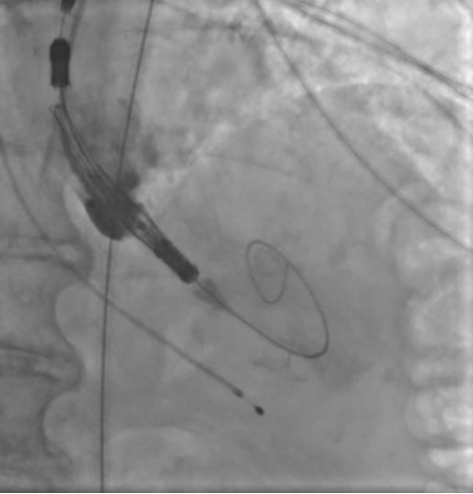

Рис. 6. Пациентка В. Ангиография корня аорты: визуализируется минимальная регургитация.

Рис. 7. Пациентка В. Баллонная предилатация.

Рис. 8. Пациентка В. В момент проведения и позиционирования искусственного клапана визуализируется умеренная регургитация.

Рис. 9. Пациентка В. Контрольная ангиография.

Процедура ТИАК выполнялась по стандартной методике, принятой в нашем центре (рис. 6-9). После предилатации баллонным катетером "Valver" 18×40 мм возникло ухудшение гемодинамики за счет развития выраженной аортальной регургитации, проявившееся снижением диастолического АД до 20 мм рт.ст. В срочном порядке была выполнена имплантация "Acurate Neo2 S" диаметром 23 мм в аортальную позицию, после чего явления гипотонии и сердечной недостаточности были компенсированы. Коронарные артерии не были скомпрометированы. После выполнения основного этапа операции интродьюсер из правой общей бедренной артерии удален, затем выполнено ушивание места доступа системой зашивающего устройства "ProGlide" (6F) и AngioSeal VIP (6F), наложен кожный шов. Ход оперативного лечения без особенностей.

Во втором клиническом случае был учтен предыдущий опыт и изменена тактика проведения вмешательства у пациентки с аналогичным фенотипом ЛЖ. Исключение этапа баллонной вальвулопластики способствовало снижению риска перегрузки ЛЖ за счет аортальной регургитации. Таким образом, на всех этапах операции у второй пациентки сохранялась разграничительная функция нативного клапана или биопротеза. В третьем клиническом случае у пациентки наблюдался массивный кальциноз АК, что не позволяло исключить этап предилатации. Поэтому было принято решение выполнить щадящую вальвулопластику для обеспечения технической возможности проведения через АК системы доставки протеза. Тем не менее даже умеренная регургитация, появившаяся после этапа предилатации, негативно повлияла на гемодинамику пациентки, которая была скорректирована лишь после имплантации биопротеза. Таким образом, у пациентки удалось избежать выраженной объемной перегрузки ЛЖ, благодаря чему удалось успешно выполнить вмешательство, не прибегая к СЛР.